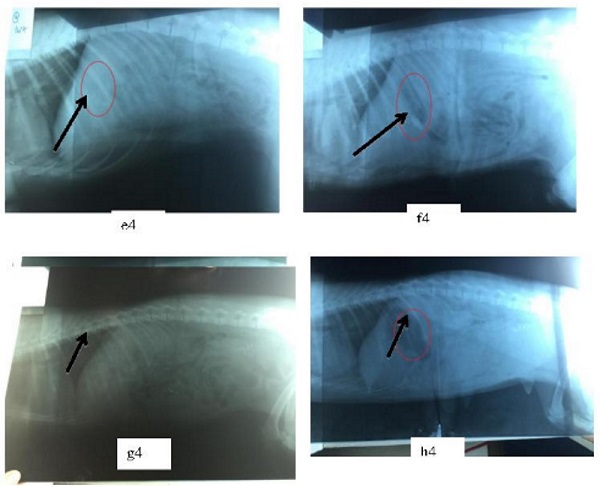

Các thử nghiệm và đánh giá trong phòng thí nghiệm cho thấy, khả năng nổi của viên Clarithromycin lên đến 12 giờ. Còn thử nghiệm trên cơ thể sống (cụ thể là trên chó) được đánh giá bằng phương pháp chụp X-quang cho thấy, khả năng nổi của viên Clarithromycin lên tới 5 giờ. Những thử nghiệm trên chó cũng chứng minh rằng, các tá dược dùng trong chế phẩm này không gây ra bất kỳ tác động độc nào cho các động vật đã được nghiên cứu.

Ảnh X-quang cho thấy viên nổi trong dạ dày của chó và duy trì được tình trạng như vậy đến 5 giờ. Ảnh: Nhóm nghiên cứu.